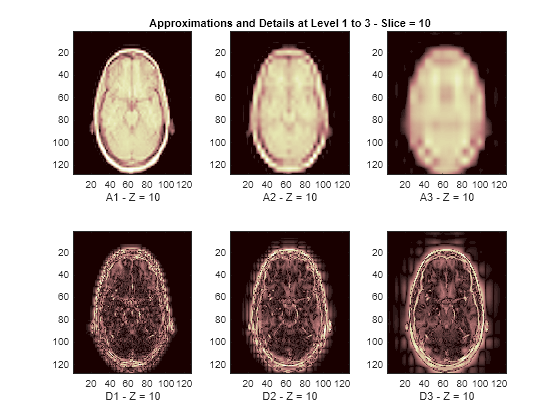

Display Lowpass and Highpass Components

The reconstructed approximations and details along the Z-orientation are displayed below.

nbIMG = 6; idxImages_New = [1 7 10 16 19 25]; for ik = 1:nbIMG j = idxImages_New(ik); figure('DefaultAxesXTick',[],'DefaultAxesYTick',[],... 'DefaultAxesFontSize',8,'Color','w') colormap(map) for k = 1:n labstr = [int2str(k) ' - Z = ' int2str(j)]; subplot(2,n,k) image(A{k}(:,:,j)) xlabel(['A' labstr]) if k==2 title(['Approximations and Details at Level 1 to 3 - Slice = ' num2str(j)]) end subplot(2,n,k+n) imagesc(abs(D{k}(:,:,j))) xlabel(['D' labstr]) end end